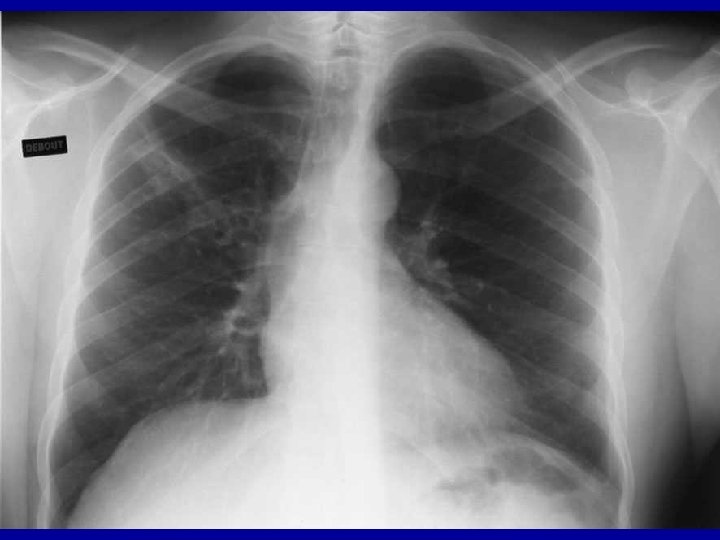

Les complications graves : SIDA • La pneumocystose – Infection pulmonaire – Clinique • En général apparition progressive • Dyspnée, toux • Image pulmonaire – Diagnostic : lavage broncho-alvéolaire – Peut être grave • mortalité 100% en l’absence de soins – Thérapeutique disponible • Triméthoprime-Sulfaméthoxazole – Fortes doses – Risques d’intolérance – Prophylaxie secondaire nécessaire (TMP-SMX)